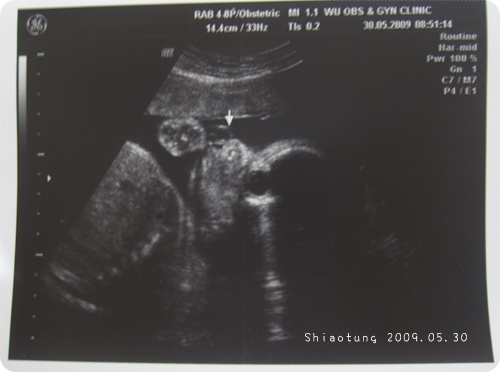

這側臉看起來好像小猴子...